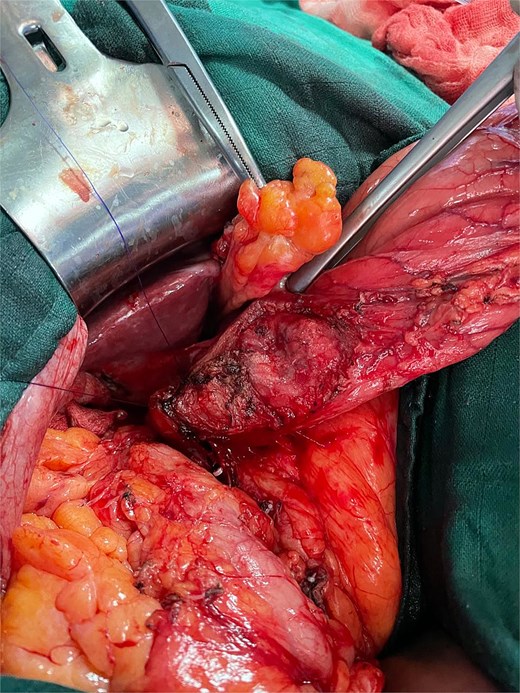

The initial laparoscopic approach was converted to right subcostal laparotomy (Fig. 2) due to unfavorable local conditions and severe inflammatory changes.

Surgical exploration revealed the true pathology: acute complicated cholecystitis with gallbladder fistulization to the subserosal gastric wall in the antro-pyloric region (Fig. 3), without mucosal involvement. The apparent ‘second gallbladder’ on imaging was actually a pseudocystic formation created by the fistulous communication and inflammatory process. The area was surrounded by significant inflammatory adhesions involving the omentum, creating a complex inflammatory mass.

Intraoperative view showing cholecystitis of a sclerotic and atrophic gallbladder associated with a cholecysto-gastric fistula.